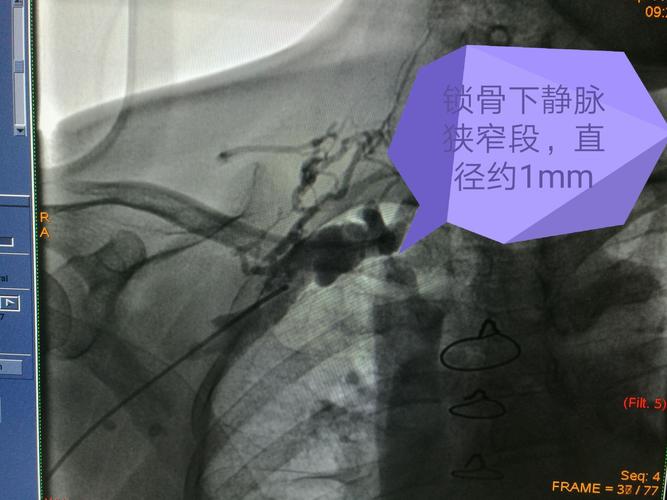

dsa下造影见锁骨下静脉跨第一肋处狭窄